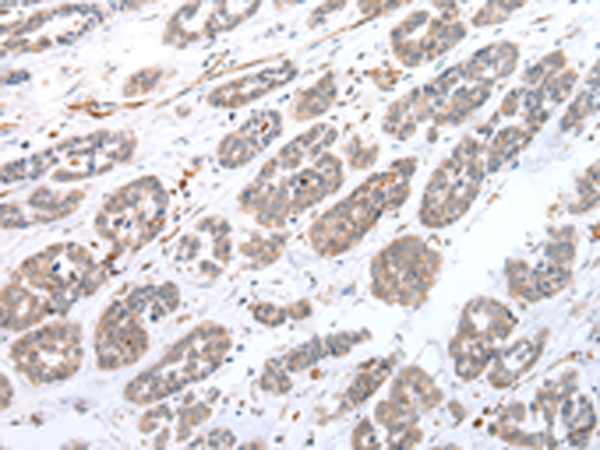

分类: 科研抗体货号: P12503别名: CATL1; CPT1P; CPTIC; SPG73; CPT1-B; CPTI-B应用: IHC反应种属: Human, Mouse, Rat